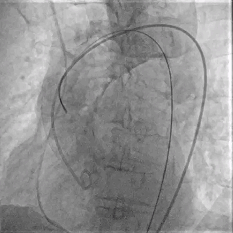

Step 4.输送系统进入:过弓性能优异,悬空通过,整体过程未将鞘管顶起至弓顶部

Step 5.瓣膜定位与释放:高起始位逐渐向下推送保持良好同轴性,无位移

Step 6.工作位观察:真实瓣环下方2mm,位置合适,决定释放,一次完成

Step 7.瓣膜脱钩:脱钩稳定无位移

过弓示意图